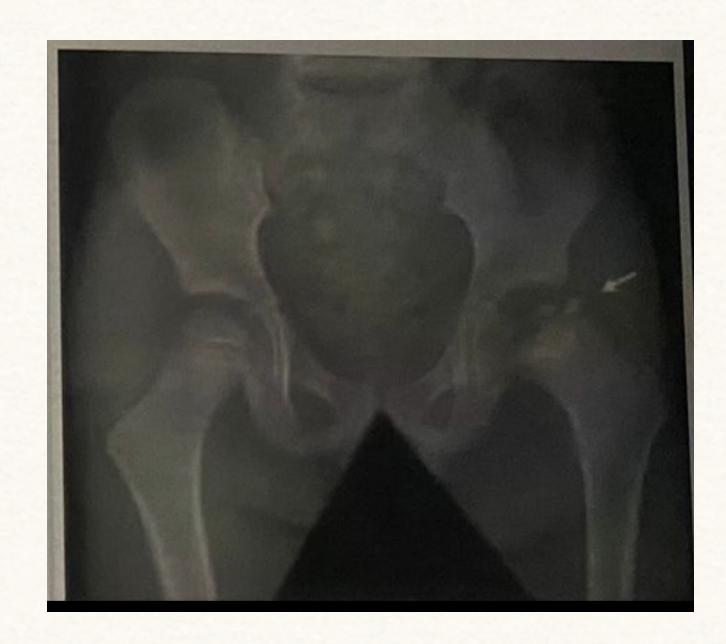

A 15-month-old child was brought to the clinic because of painless limping. There is no history of trauma. The pelvic x-ray is shown.

Q1: Write two abnormalities seen on the X-ray.

- Lateralization of the ossifying centre

- Acetabular angle more than 27ยฐ

- Broken Shenton line

- Shortening of the line from greater trochanter to the horizontal line

Q2: What is the most probable diagnosis?

- Developmental dysplasia of the hip (DDH)